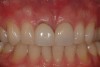

Fig 26. The results of this esthetic treatment is an inconspicuous implant-supported crown restoration.

Figure 26